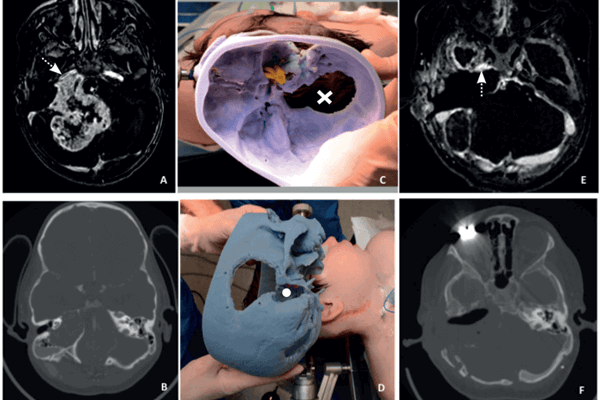

The utilisation of three-dimensional printed models in skull base surgery